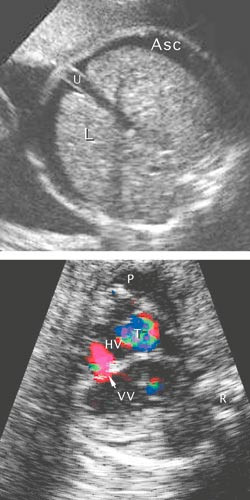

Pasient 3. En gravid kvinne ble syk i 12. svangerskapsuke med feber, utslett og senere leddsmerter. I serum fra mor ble det etter hvert påvist IgG- og IgM-antistoff mot parvovirus B19, forenlig med aktuell infeksjon. Da hun i 25. svangerskapsuke kjente mindre liv, ble hun utredet nærmere og fikk påvist føtal ascites (fig 1), subkutant ødem, placentaødem, leverforstørrelse, intrakraniale forandringer forenlig med hjerneødem, ekkogene nyrer og tom urinblære. Kardiomegali, perikardeffusjon, lekkasje gjennom mitral- og trikuspidalklaffen og økt pulsatilitet i prekordiale vener tydet på hjertesvikt (fig 2). Forhøyede blodstrømshastigheter i a. cerebri media tydet på anemi. Blodprøve fra navlesnoren bekreftet anemi (Hb 1,9 g/100 ml) og trombocytopeni (Trc 17 · 10⁹/l). Fosteret fikk transfusjoner, men døde. Underveis hadde det utviklet seg ventrikkelseptumdefekt (fig 1). Parvovirus B19-DNA ble påvist ved polymerasekjedereaksjon i fosterblod, fostervann og placenta samt i mors serum.

Siden tilstanden kan behandles, bør det ved kjent eller mistenkt eksposisjon utføres serologisk diagnostikk av gravide kvinner. Deteksjonsraten med denne metoden er 81,3 % (14, 15). Dersom IgM-antistoff mot parvovirus B19 påvises, er dette tilstrekkelig grunnlag for henvisning til spesialavdeling. I føtalt blod er sensitiviteten av serologiske undersøkelser lav (43,8 %). Dopplermålinger i fosterhjerne, hjerte, ductus venosus, umbilikalvene og -arterie gir en oversikt over fosterets sirkulatoriske situasjon og kan avdekke anemi (16, 17), myokardaffeksjon og portahypertensjon (18). Påvisning av parvovirus B19-DNA med polymerasekjedereaksjon er en sensitiv metode og kan utføres i mors blod, fostervann, placenta eller navleveneblod. På grunn av risiko for komplikasjoner vil kordocentese vanligvis bare bli gjort i tilfeller der det er berettiget mistanke om anemi.